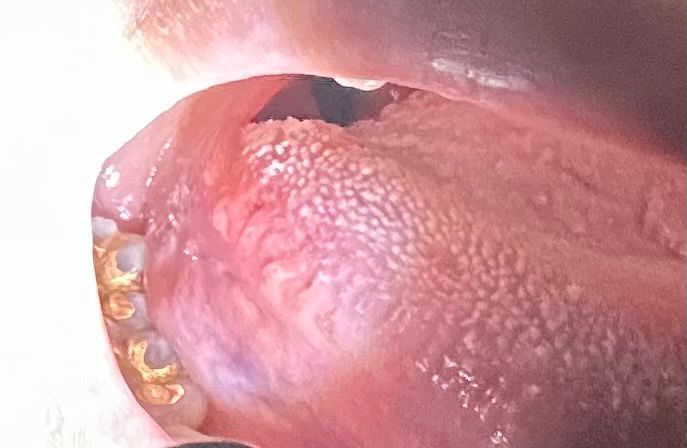

제 혀의 증상이 설암인지 걱정됩니다. 아니라면 왜 이런 걸까요.

6월 초부터 혀에 이상한 감각이 느껴지다가 6월 13일경 혀 오른쪽 측면의 안쪽에 돌기가 이상하게 튀어나온 것을 발견했습니다. 처음에는 궤양인 줄 알았으나 궤양은 아니었고 엽상유두 돌기 부분이 약간 패인 듯한 부분과 튀어나온 부분이 있었어요. 그 뒤로 내과, 이비인후과, 치과를 전전하면서 항생제, 소염제, 가글 등을 했고 오른쪽의 돌기는 좀 가라앉는 것 같았습니다.

그런데 돌기가 가라앉으면서 그 아래부분(혓바닥쪽과 연결되는 부분)이 붓고 통증이 생겼어요. 그리고 왼쪽에도 엽상유두 돌기가 더 튀어나왔습니다.

혀 아래쪽이 부은 증상은 2-3주 정도 되었고 어제 오늘은 통증이 심해졌습니다. 이게 먼저 생겼던 돌기의 염증이 회복되는 과정 중에 있는 것일까요 아니면 더 심각해진 것일까요. 지금 통증이 있는 부위는 딱딱하거나 출혈이 있지는 않습니다.

가장 최근에 갔던 치과의 구강악전문의 분깨서는 지금 증상이 전암성병변으로 보이지 않고 현재로서는 조직검사가 득보다 실이 클 것 같다고 하셨는데 이대로 있어도 되는걸까요. 어제 밤부터 구내염 인두염용 가글(이바프텐)을 하고 있는데 통증은 약간 줄어든 것 같지만 암은 아닐지, 더 큰 병원으로 가서 조직검사를 받아봐야 할지 걱정이 됩니다.

만약에 암은 아닌 것 같다면 왜 이런 증상이 계속되는 것인지, 저 부분이 혀의 구조에서 어떤 부분에 해당하는 것인지, 이번에 다시 병원을 방문해도 지켜보자고 하시면 조직검사를 꼭 받고 싶다고 강하게 요청해야 하는 것일지 선생님들의 의견을 부탁드립니다.

• 1번 째 사진

물론 직접 병소를 본 의사가 더 잘 파악했겠지만 지금 사진상으론 verruciform xanthoma 가 의심됩니다. 대학치과병원가서 조직검사 해보세요

몸의 면역력이 떨어지게 되면 점막조직이 약해 지게 되고 외부자극에 쉽게 손상이 될수 있습니다. 사진을 봤을 경우에는 크게 문제가 되는것으로 보이지는 않습니다.